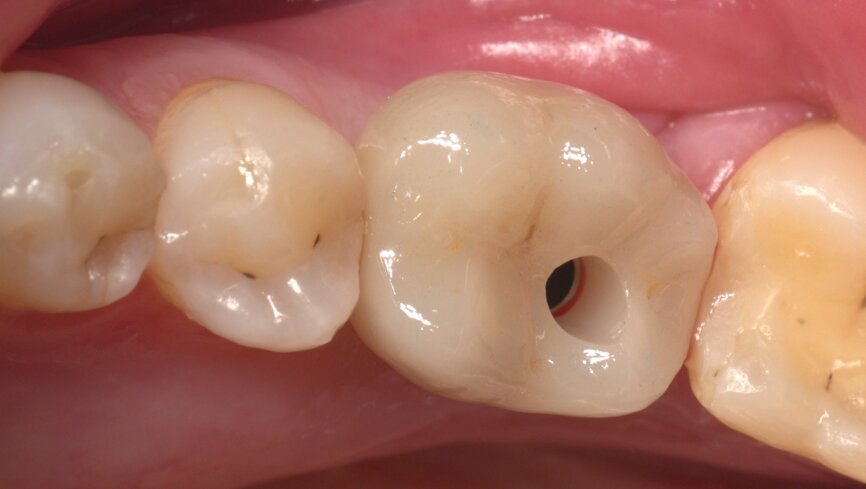

A BLT implant (Regular Neck, Roxolid, ⌀ 4.1 × 12.0 mm) was placed in position #15. As the insertion torque value and Implant Stability Quotient (ISQ) level were not optimal for immediate loading, a delayed protocol with a healing cap was selected.

Two months later, a panoramic radiograph showed an excellent situation for the BLT implant and correct healing of position #36 (Fig. 1). Following a chairside protocol, it was decided to load implant #15 and provide an implant treatment with immediate loading in position #36 on the same day. This involved the design of two screw-retained crowns with the TRIOS Design Studio software, and their production in n!ce material on the C series milling unit.